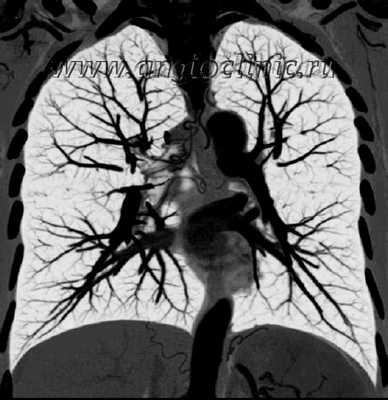

Ангиопульмонография - метод рентгенологической диагностики состояния лёгочного кровообращения путём введения рентгеноконтрастных веществ в артерии лёгких. Выделяют общую и селективную ангиопульмонографию. При общей ангиопульмонографии контрастное вещество вводят в ствол лёгочной артерии, при этом заполняются все сосуды малого круга кровообращения. При селективной контраст вводится лишь в одну из ветвей лёгочной артерии и оценивается состояние кровотока только одного лёгкого или его доли.

Во время выполнения ангиопульмонографии пациент лежит на операционном столе. Перед началом исследования пациенту делают местную анестезию. После пункции бедренной вены (прокола её стенки), в неё вводят проводник, по которому затем проходит катетер. Катетер проводят через правые отделы сердца, сначала в предсердие, из него в желудочек, откуда катетер попадает в ствол лёгочной артерии. Если выполняется общая ангиопульмонография, то в этом месте начинают введение контрастного вещества. Для селективной ангиопульмонографии необходимо провести катетер в одну из ветвей легочной артерии - правую или левую. Для диагностики тромбоэмболии легочной артерии или тромба в нижней полой вене применяют доступ через подключичную вену или внутреннюю яремную вену.

Во время введения контрастного вещества в лёгочную артерию у пациента может появится чувство прилива крови к лицу, солёный привкус во рту. Одновременно с введением контраста выполняется скоростная рентгеновская съёмка в двух проекциях. В результате получается серия снимков, которые можно хранить в памяти компьютера и просматривать повторно.

Интерпретация результатов ангиопульмонографии

- При оценке результатов исследования обнаруживают патологические изгибы сосудов лёгких, участки их сужения, расширения, наличие дополнительных ветвей.

- При тромбоэмболии легочной артерии на снимке точно виден тромб, можно определить его размеры и локализацию.

- По характеру сосудистого рисунка можно судить о наличии опухоли в лёгком.

Таким образом, ангиопульмонография является золотым стандартом в диагностике тромбоэмболии легочной артерии, так как не только подтверждает наличие либо отсутствие тромба, но и определяет локализацию и размеры.

Ангиопульмонография - рентгеновское исследование легочных артерий, применяемое для выявления причин легочной гипертензии. Всем пациентам до операции на легочных артериях для оценки состояния легочного русла должна выполняться ангиопульмонография в двух проекциях.

Как проводится ангиография легких

Ангиогпульмонография начинается с выполнения пункции правой подключичной или яремной вены, в которую устанавливается интродьюсер 6 FR. По интродьюсеру на проводнике при помощи диагностических катетеров катетеризируются правые отделы сердца. Диагностический катетер устанавливается в легочный ствол в область бифуркации правой и левой главных легочных артерий. При помощи автоматического инжектора в легочную артерию вводится контраст. Далее для визуализации правой ЛА катетер устанавливается в правую главную ЛА и вводилось 40 мл контраста. Для визуализации левой ЛА катетер устанавливается в левую главную ЛА и вводится тот же объем контраста. Во время введения контраста пациент задерживает дыхание, хирург выполняет исследование легочной артерии в двух проекциях.